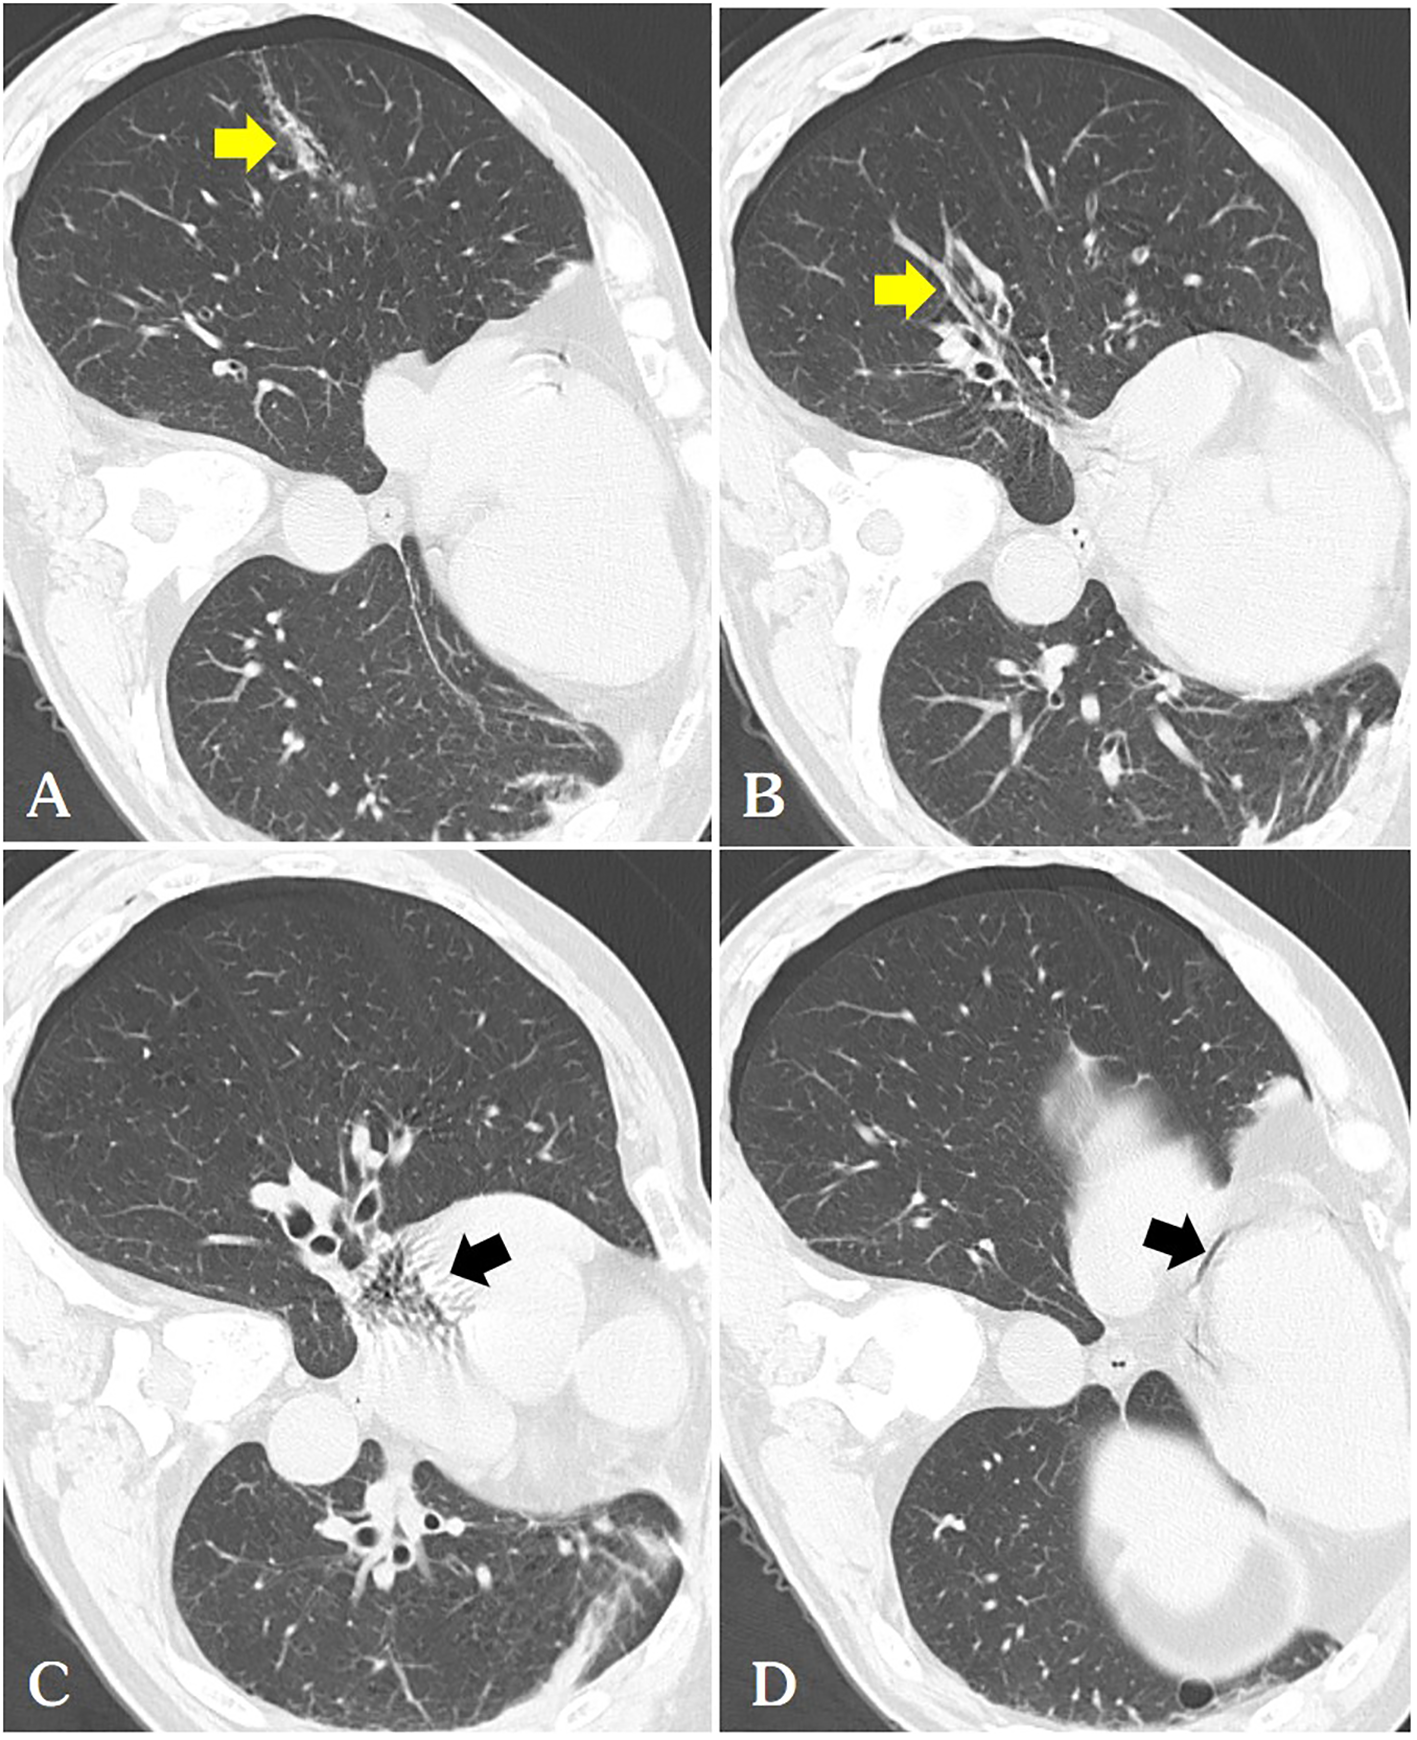

Figure 2

(A) We routinely perform a follow-up chest CT immediately after ablation, where we can observe a thicker needle tract(arrow) connecting the pneumothorax with the pulmonary vein [(B, arrow)] and pulmonary artery, hence air is observed in the right atrium [(C arrow)] and coronary arteries [(D arrow)].

Various mechanisms may explain the entry of air into the coronary artery during surgery. The device uses only a microwaveable antenna, and air in the pleural cavity indirectly enters the pulmonary vein through the puncture needle track. Additionally, intra-alveolar or intra-bronchial air may enter the pulmonary venous circulation. A third potential mechanism is the entry of air into the pulmonary arterial circulation, which subsequently traverses the pulmonary microvasculature to reach the pulmonary venous circulation, even in the absence of an arteriovenous malformation. Our sole explanation for the presence of air in the pulmonary veins is the puncture tract connected the pneumothorax with the pulmonary veins, allowing air to transit between the two (Figure 2A). The pulmonary veins expel air directly into the left atrium and left ventricle, subsequently entering the body circulation and coronary arteries.